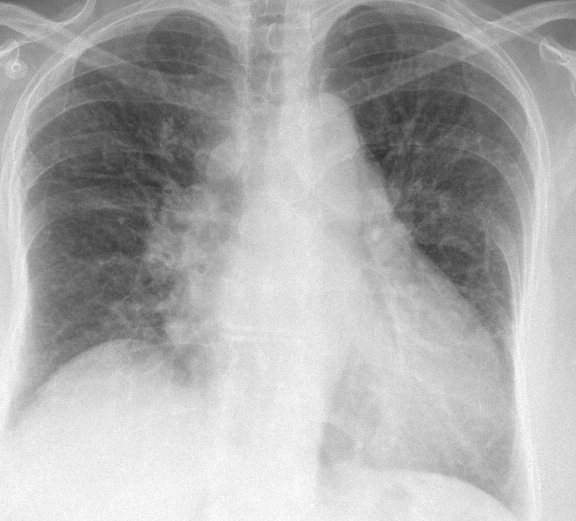

Gallery Cardiac Heart failure Bivent failure

Bivent failure